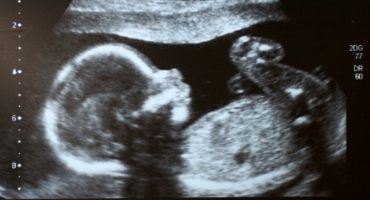

הריון תאומים

הריון הוא תמיד אירוע מרגש, אבל כאשר מדובר בהריון של שני עוברים ויותר, זו כבר בכלל סיבה לחגיגה. פרופ' רוני מימון, מנהל חטיבת נשים ויולדות במרכז הרפואי "שמיר" (אסף הרופא), מסביר על המורכבות שבהריון תאומים ואפילו מציע לכן לקחת חלק במחקר פורץ דרך בתחום